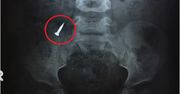

29-letnia Holly Smith martwiła się, gdyż jej córka od kilku dni źle się czuła. Dziewczyna była ospała i zmęczona. Gdy wieczorem kobieta zauważyła, że nastolatka z trudem wstaje z kanapy, wezwała pogotowie. Okazało się, że złe samopoczucie 11-latki wynikało z palenia e-papierosów. [image type="big" title="Liczba dzieci, które regularnie palą e-papierosy, podwoiła się w ciągu ostatnich dwóch lat" source="Facebook" link="" image="https://portal-abczdrowie.wpcdn.pl/2022/07/18/zdjwa_b0a4.jpg" width="1180" height="979" x="" y="" x2="" y2="" croppedPath="https://portal-abczdrowie.wpcdn.pl/imageCache/2022/07/18/zdjwa_b0a4.-x0y0xx0yy0.jpg" ]